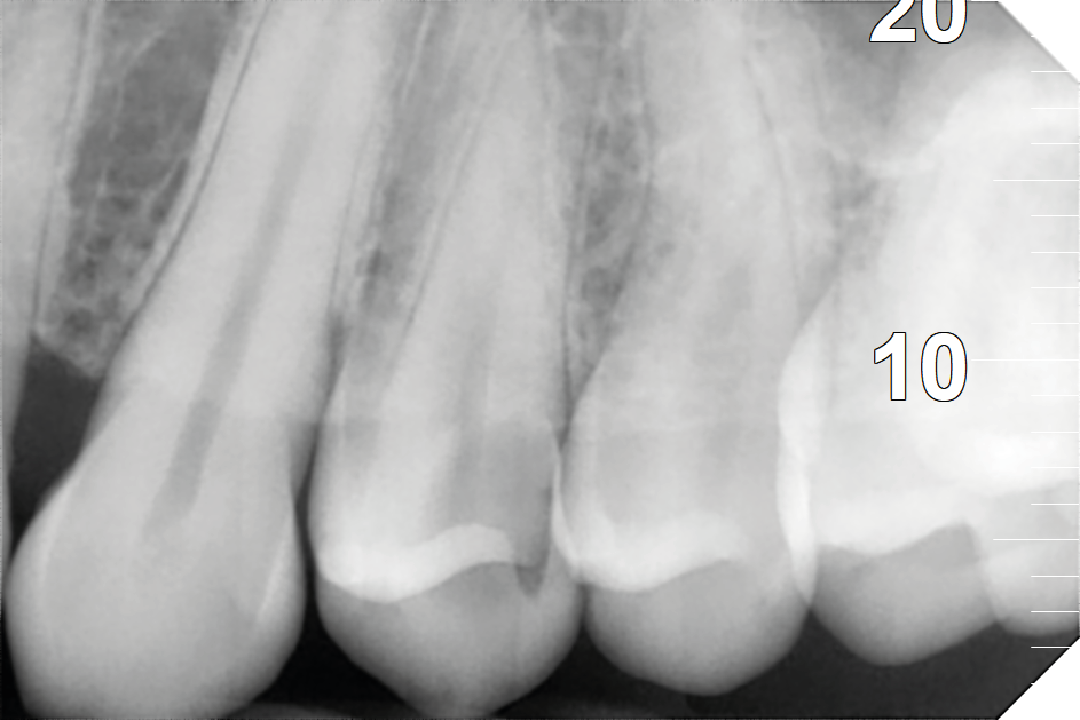

Todos los dientes tienen una cámara pulpar donde está el nervio del diente, pero cuando se afecta por una caries extensa o un traumatismo (entre otros motivos), va destruyendo progresivamente todas las estructuras hasta provocar su necrosis o muerte.

-NADA, puede que no haya dolor ni nada a simple vista pero en un examen radiográfico vemos

el origen del problema